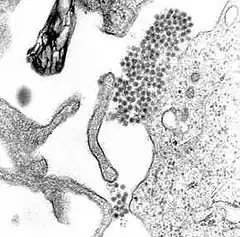

L'agent est le virus de la dengue, un virus à ARN enveloppé, appartenant au genre des flavivirus. Ce genre comprend également les virus de la fièvre jaune, de l'encéphalite japonaise, et du Nil occidental.

Il existe quatre sérotypes distincts du virus de la dengue : DENV-1, DENV-2, DENV-3 et DENV-4[14]. Ils sont étroitement apparentés et entraînent les mêmes signes cliniques.